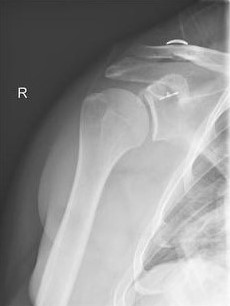

Ist nur der Oberarmkopf beschädigt, die Gelenkpfanne jedoch intakt, kann der betroffene Knochen überkront werden. Dabei wird die Oberfläche des natürlichen Knochens exakt nachgebildet und auf dem Knochen angebracht. Die Fixierung erfolgt entweder mit speziellem Knochenzement oder wird genau passend an der betroffenen Stelle durch Andrücken fixiert. Das darunter liegende gesunde Knochengewebe wächst im Heilungsverlauf in den teilweisen Gelenkersatz ein, sodass dieser festwächst.

Alternativ dazu lässt sich der Oberarmkopf gänzlich nachbilden und mittels eines Schaftstils im Oberarmknochen fixieren. Die Wahl der für den Patienten am besten geeigneten Prothese orientiert sich an verschiedenen Faktoren, unter anderem die individuelle Anatomie des zu behandelnden Gelenks und der Qualität der Knochen.

Totalendoprothese

Ist die Arthrose sowohl am Oberarmkopf als auch an der Gelenkpfanne fortgeschritten, empfiehlt es sich, eine Totalendoprothese (TEP) einzusetzen. Dabei werden beide Gelenkpartner künstlich nachgebildet, um den natürlichen Bewegungsmechanismus wiederherzustellen. Die Basis dafür ist eine hohe Passgenauigkeit der Prothese. Diese wird, wie auch bei der Teilendoprothese, durch eine exakte Planung und individuelle Anpassung des Gelenkersatzes entsprechend der patienteneigenen Anatomie gewährleistet.